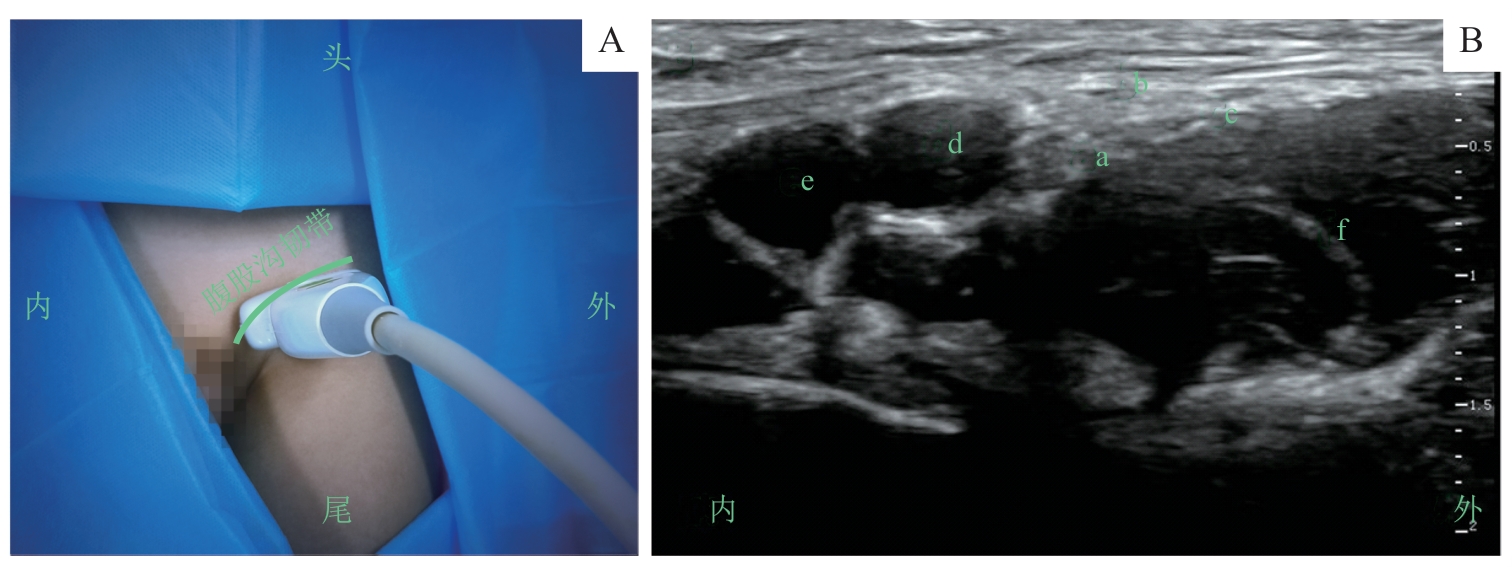

图3 股神经阻滞的超声定位和影像Note: A. 超声探头体表扫描定位/Surface scanning for ultrasound probe positioning. B. 探头处于图A位置时的股神经超声影像/Ultrasound image of the femoral nerve obtained with the probe positioned as shown in figure A. a—股神经/femoral nerve; b—阔筋膜/fascia lata; c—髂筋膜/fascia iliac; d—股动脉/femoral artery; e—股静脉/femoral vein; f—髂腰肌/iliopsoas muscle.

Fig 3 Ultrasound positioning and imaging of the femoral nerve block